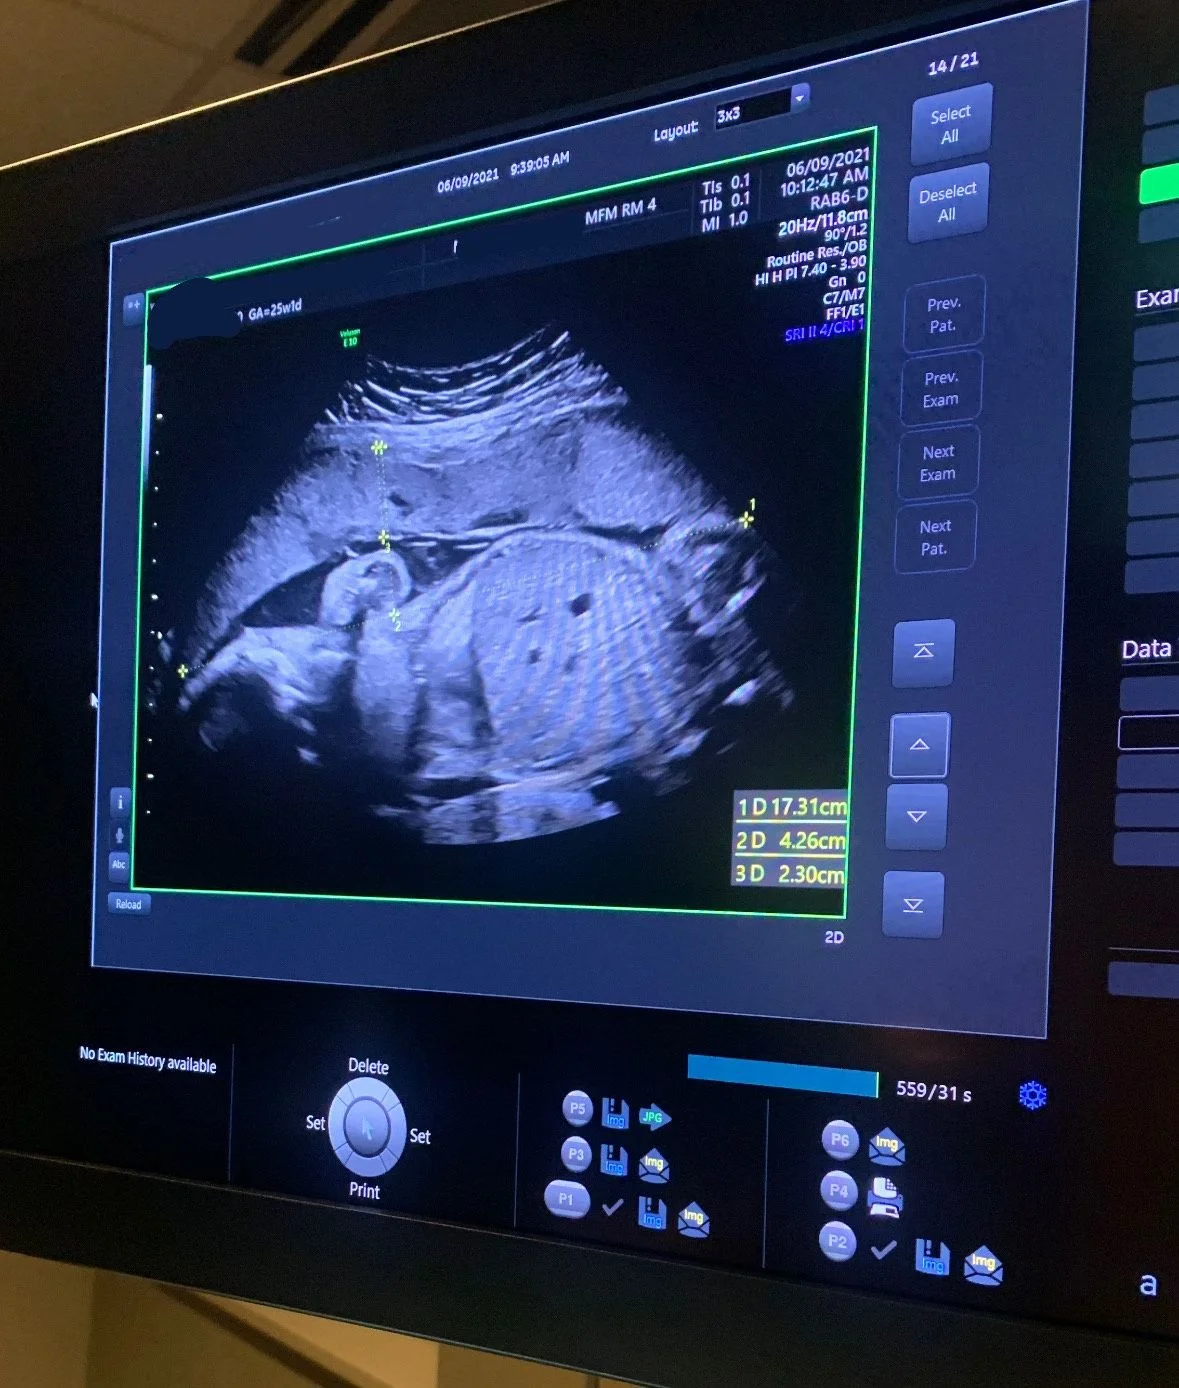

This baby’s placenta dropped below the 10th percentile by 32 weeks gestation.

Tragically, the placenta was not measured during pregnancy. Standard biophysical profiles showed a healthy pregnancy. The child was stillborn at full term.

This chart was created retroactively with ultrasounds on file. It likely would have indicated induction - and saved a life.